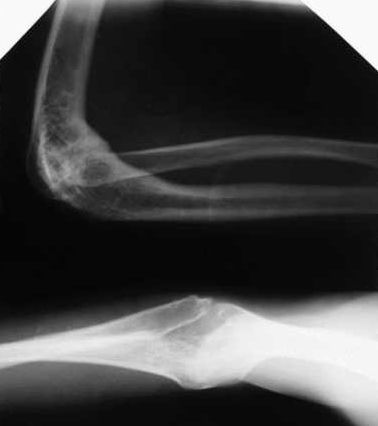

Анкилоз локтевого сустава у ребенка 13лет |

Здравствуйте, уважаемые коллеги. Обратился пациент 13 лет с анкилозом левого локтевого сустава, после остеомиелита . Несколько лет тому назад больному пытались сохранить сустав в одной клинике. из документов известно, что резецировали головку лучевой кости и сформировали блок плечевой кости. На сегодняшний день: локтевой сустав в положении сгибания 80гр. просупинационные движения 10/0/10. Пациент не может самостоятельно надеть ботинки и застегнуть брюки. Я планирую выполнить коррегирующую разгибательную остеотомию плечевой кости в н/3